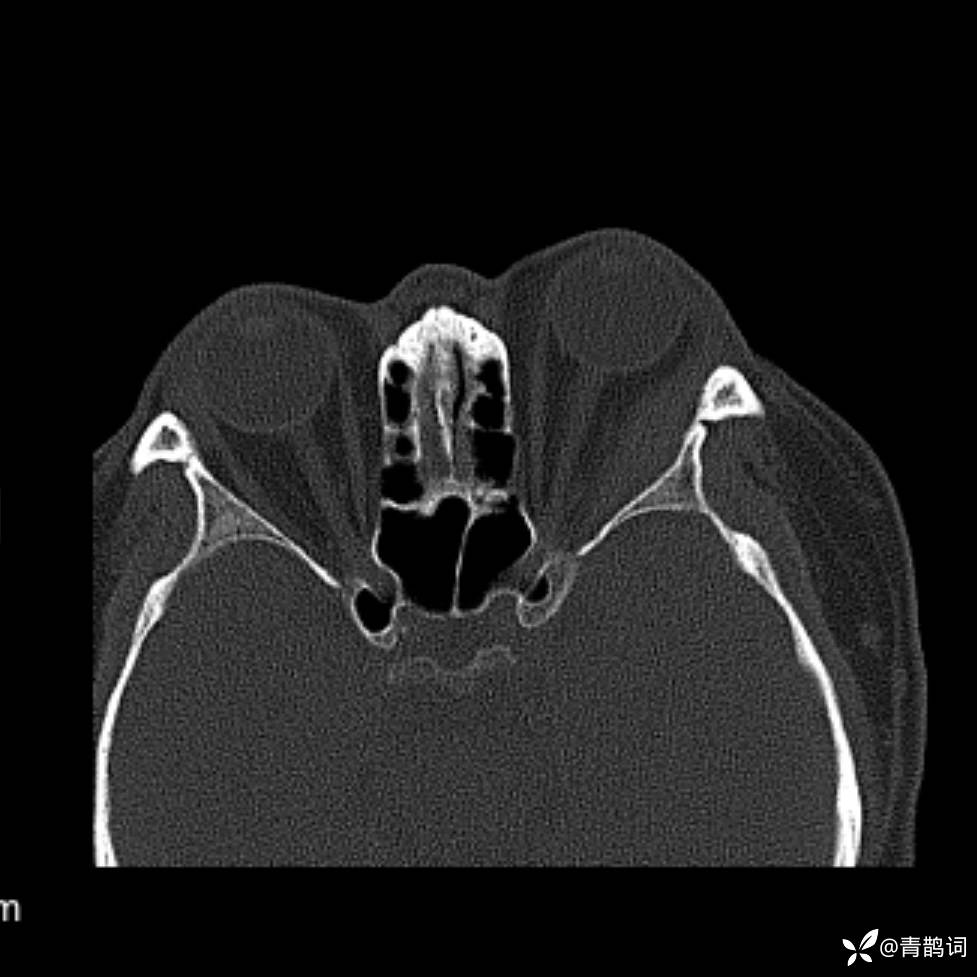

患者年龄:30岁。

患者性别:男。

简要病史:左颜面部肿胀2年,反复咳嗽咳痰,逐渐加重。

辅助检查

结合病史及影像学表现,期待评论区各位老师各抒己见~